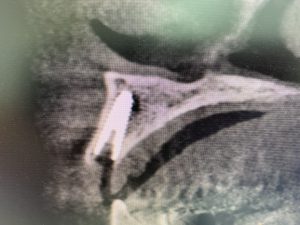

午前中の一件目は猪子副院長による下顎小臼歯インプラントオペ

上顎前歯症例のオペ

下顎大臼歯症例のオペ